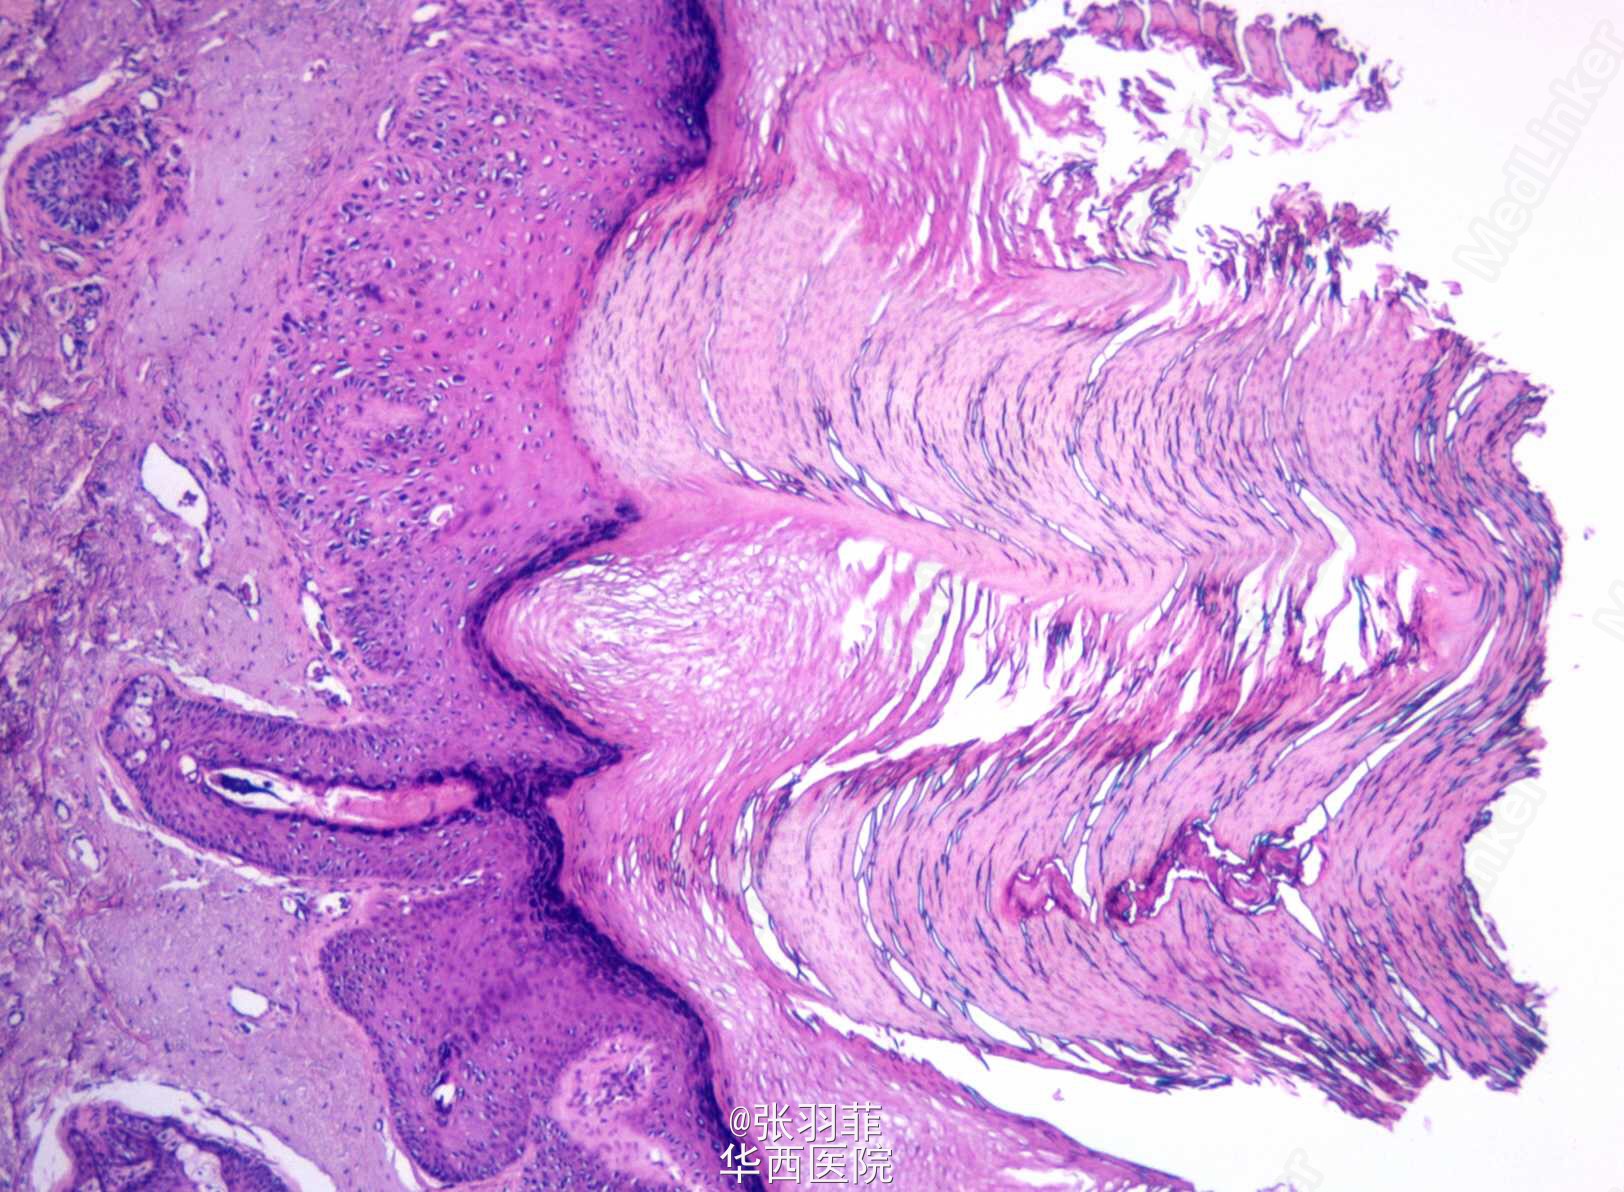

日光性角化病是日光相关的角化异常,主要发生于暴光部位,皮损为褐色角化性斑片,表面覆以不易剥离的黑褐色鳞屑。一般认为是癌前病变,有恶化鳞癌的可能。

而皮角是一种形态学诊断,也被认为是癌前病变,多发生在某些皮肤病如脂溢性角化病、日光性角化病的基础上,由于病损处角质物异常增多而形成突起状角化性皮损,形似动物的角。